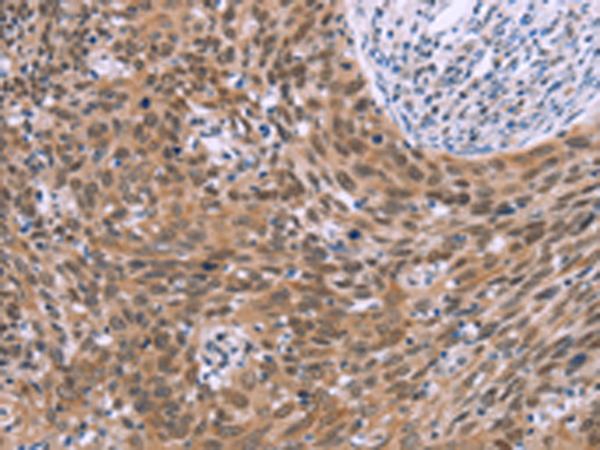

分类: 科研抗体货号: P04874别名: F1AA; F1A-ALPHA; FEM1-beta应用: WB,IHC反应种属: Human, Mouse, Rat